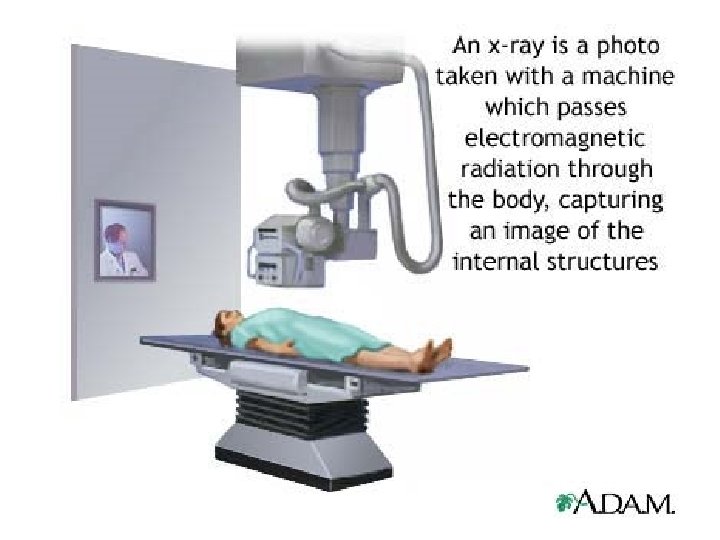

How RADIOGRAPHS (X-RAYS) ARE MADE • X-rays created in an x-ray tube – controlled by the technologist • Patient is placed into a position to see the anatomy best • Radiation passes through and leaves an impression on the film inside of the x-ray cassette

How RADIOGRAPHS (X-RAYS) ARE MADE • X-rays created in an x-ray tube – controlled by the technologist • Patient is placed into a position to see the anatomy best • Radiation passes through and leaves an impression on the film inside of the x-ray cassette

X-rays can provide information about: • Obstructions (blockage) • Tumors • Fractures • Other diseases & illnesses

X-rays can provide information about: • Obstructions (blockage) • Tumors • Fractures • Other diseases & illnesses